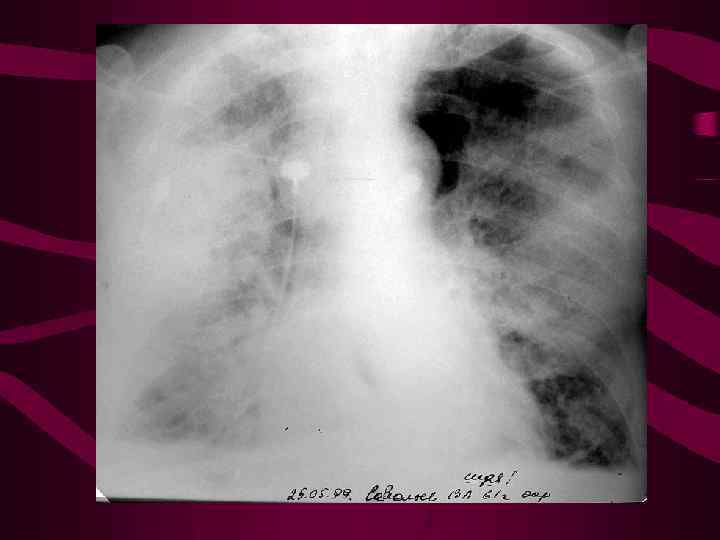

Хроническая ТЭЛА. Воздушность в нижней доле слева повышена, сосудистый рисунок обеднен. Справа картина альвеолярного отека.

Хроническая ТЭЛА. Воздушность в нижней доле слева повышена, сосудистый рисунок обеднен. Справа картина альвеолярного отека.